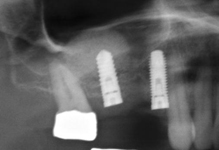

Při ztrátě molárů a premolárů v horní čelisti a jejich náhradě implantáty se často setkáváme s nedostatečnou vertikální nabídkou kosti pod čelistní dutinou, často doprovázenou i nedostatečnou horizontální nabídkou a sníženou kvalitou kosti

(v oblasti 2. premoláru v 50%, v oblasti moláru až v 80% případů nedostatečná kostní nabídka)

Od roku 1985 je tento problém řešen augmentační operací nazývanou sinus lift.

Jedná se o vyzvednutí membrány, která čelistní dutinu vystýlá, pod vyzvednutou membránou vznikne kapsa, kam se umístí augmentační materiál, do kterého se zavedou implantáty.

Vhojení implantátů se při této operaci prodlužuje na 6-12 měsíců.